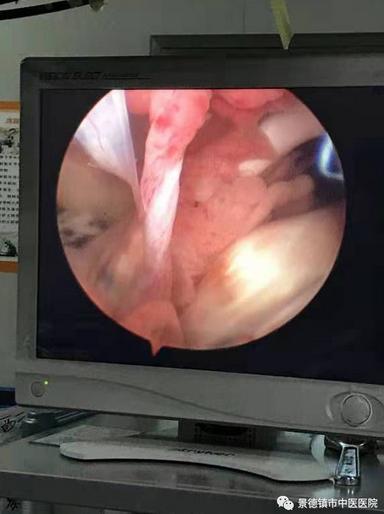

手術(shù)半月板縫合+前叉韌帶重建前

半月板“桶柄樣”撕裂

前交叉韌帶斷裂